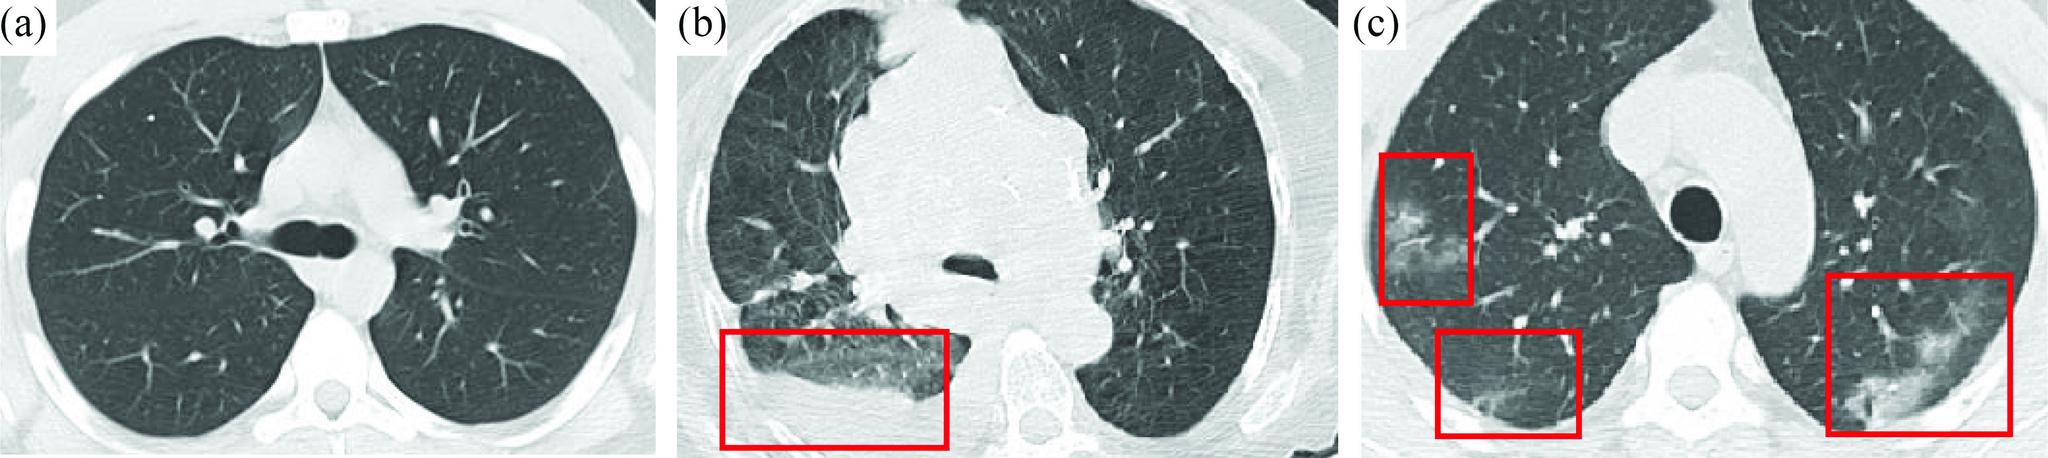

As COVID-19 hounds the world, the common cause of finding a swift solution to manage the pandemic has brought together researchers, institutions, governments, and society at large. The Internet of Things (IoT), artificial intelligence (AI)-including machine learning (ML) and Big Data analytics-as well as Robotics and Blockchain, are the four decisive areas of technological innovation that have been ingenuity harnessed to fight this pandemic and future ones. While these highly interrelated smart and connected health technologies cannot resolve the pandemic overnight and may not be the only answer to the crisis, they can provide greater insight into the disease and support frontline efforts to prevent and control the pandemic. This article provides a blend of discussions on the contribution of these digital technologies, propose several complementary and multidisciplinary techniques to combat COVID-19, offer opportunities for more holistic studies, and accelerate knowledge acquisition and scientific discoveries in pandemic research. First, four areas, where IoT can contribute are discussed, namely: 1) tracking and tracing; 2) remote patient monitoring (RPM) by wearable IoT (WIoT); 3) personal digital twins (PDTs); and 4) real-life use case: ICT/IoT solution in South Korea. Second, the role and novel applications of AI are explained, namely: 1) diagnosis and prognosis; 2) risk prediction; 3) vaccine and drug development; 4) research data set; 5) early warnings and alerts; 6) social control and fake news detection; and 7) communication and chatbot. Third, the main uses of robotics and drone technology are analyzed, including: 1) crowd surveillance; 2) public announcements; 3) screening and diagnosis; and 4) essential supply delivery. Finally, we discuss how distributed ledger technologies (DLTs), of which blockchain is a common example, can be combined with other technologies for tackling COVID-19.

随着新冠疫情席卷全球,迅速找到应对这一流行病的解决方案这一共同目标,将研究人员、机构、政府以及整个社会凝聚在了一起。物联网(IoT)、人工智能(AI)——包括机器学习(ML)和大数据分析——以及机器人技术和区块链,是技术创新的四个关键领域,人们巧妙地利用这些技术来抗击这场疫情以及未来的疫情。虽然这些高度相关的智能互联健康技术无法在一夜之间解决疫情,也可能不是应对危机的唯一答案,但它们可以提供对该疾病更深入的了解,并支持一线的疫情防控工作。本文综合讨论了这些数字技术的贡献,提出了几种应对新冠疫情的互补性多学科技术,提供了进行更全面研究的机会,并加速了疫情研究中的知识获取和科学发现。首先,讨论了物联网可以发挥作用的四个领域,即:1)追踪与溯源;2)通过可穿戴物联网(WIoT)进行远程患者监测(RPM);3)个人数字孪生(PDT);4)实际用例:韩国的信息通信技术/物联网解决方案。其次,解释了人工智能的作用和新应用,即:1)诊断与预后;2)风险预测;3)疫苗与药物研发;4)研究数据集;5)早期预警与警报;6)社会管控与假新闻检测;7)通信与聊天机器人。第三,分析了机器人技术和无人机技术的主要用途,包括:1)人群监测;2)公共公告;3)筛查与诊断;4)基本物资配送。最后,我们讨论了分布式账本技术(DLT),区块链就是其常见示例之一,如何与其他技术相结合来应对新冠疫情。